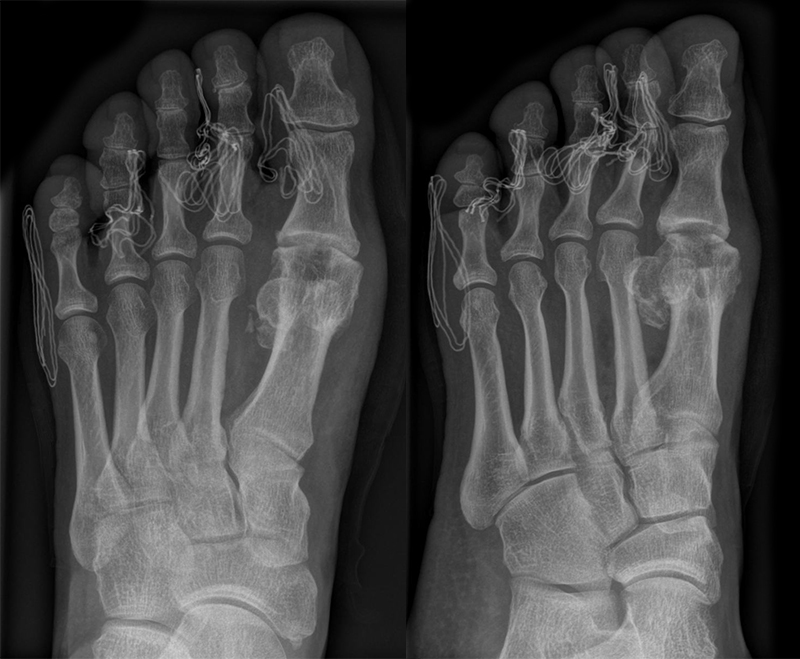

• Röntgen: Fuß belastet in 3 Ebenen.

• Optional MRT und CT bei radiologisch unklaren Verhältnissen.

Zum Lesen der Bildbeschreibung und zur Vollansicht bitte die Bilder anklicken (Fotos: M. Walther).